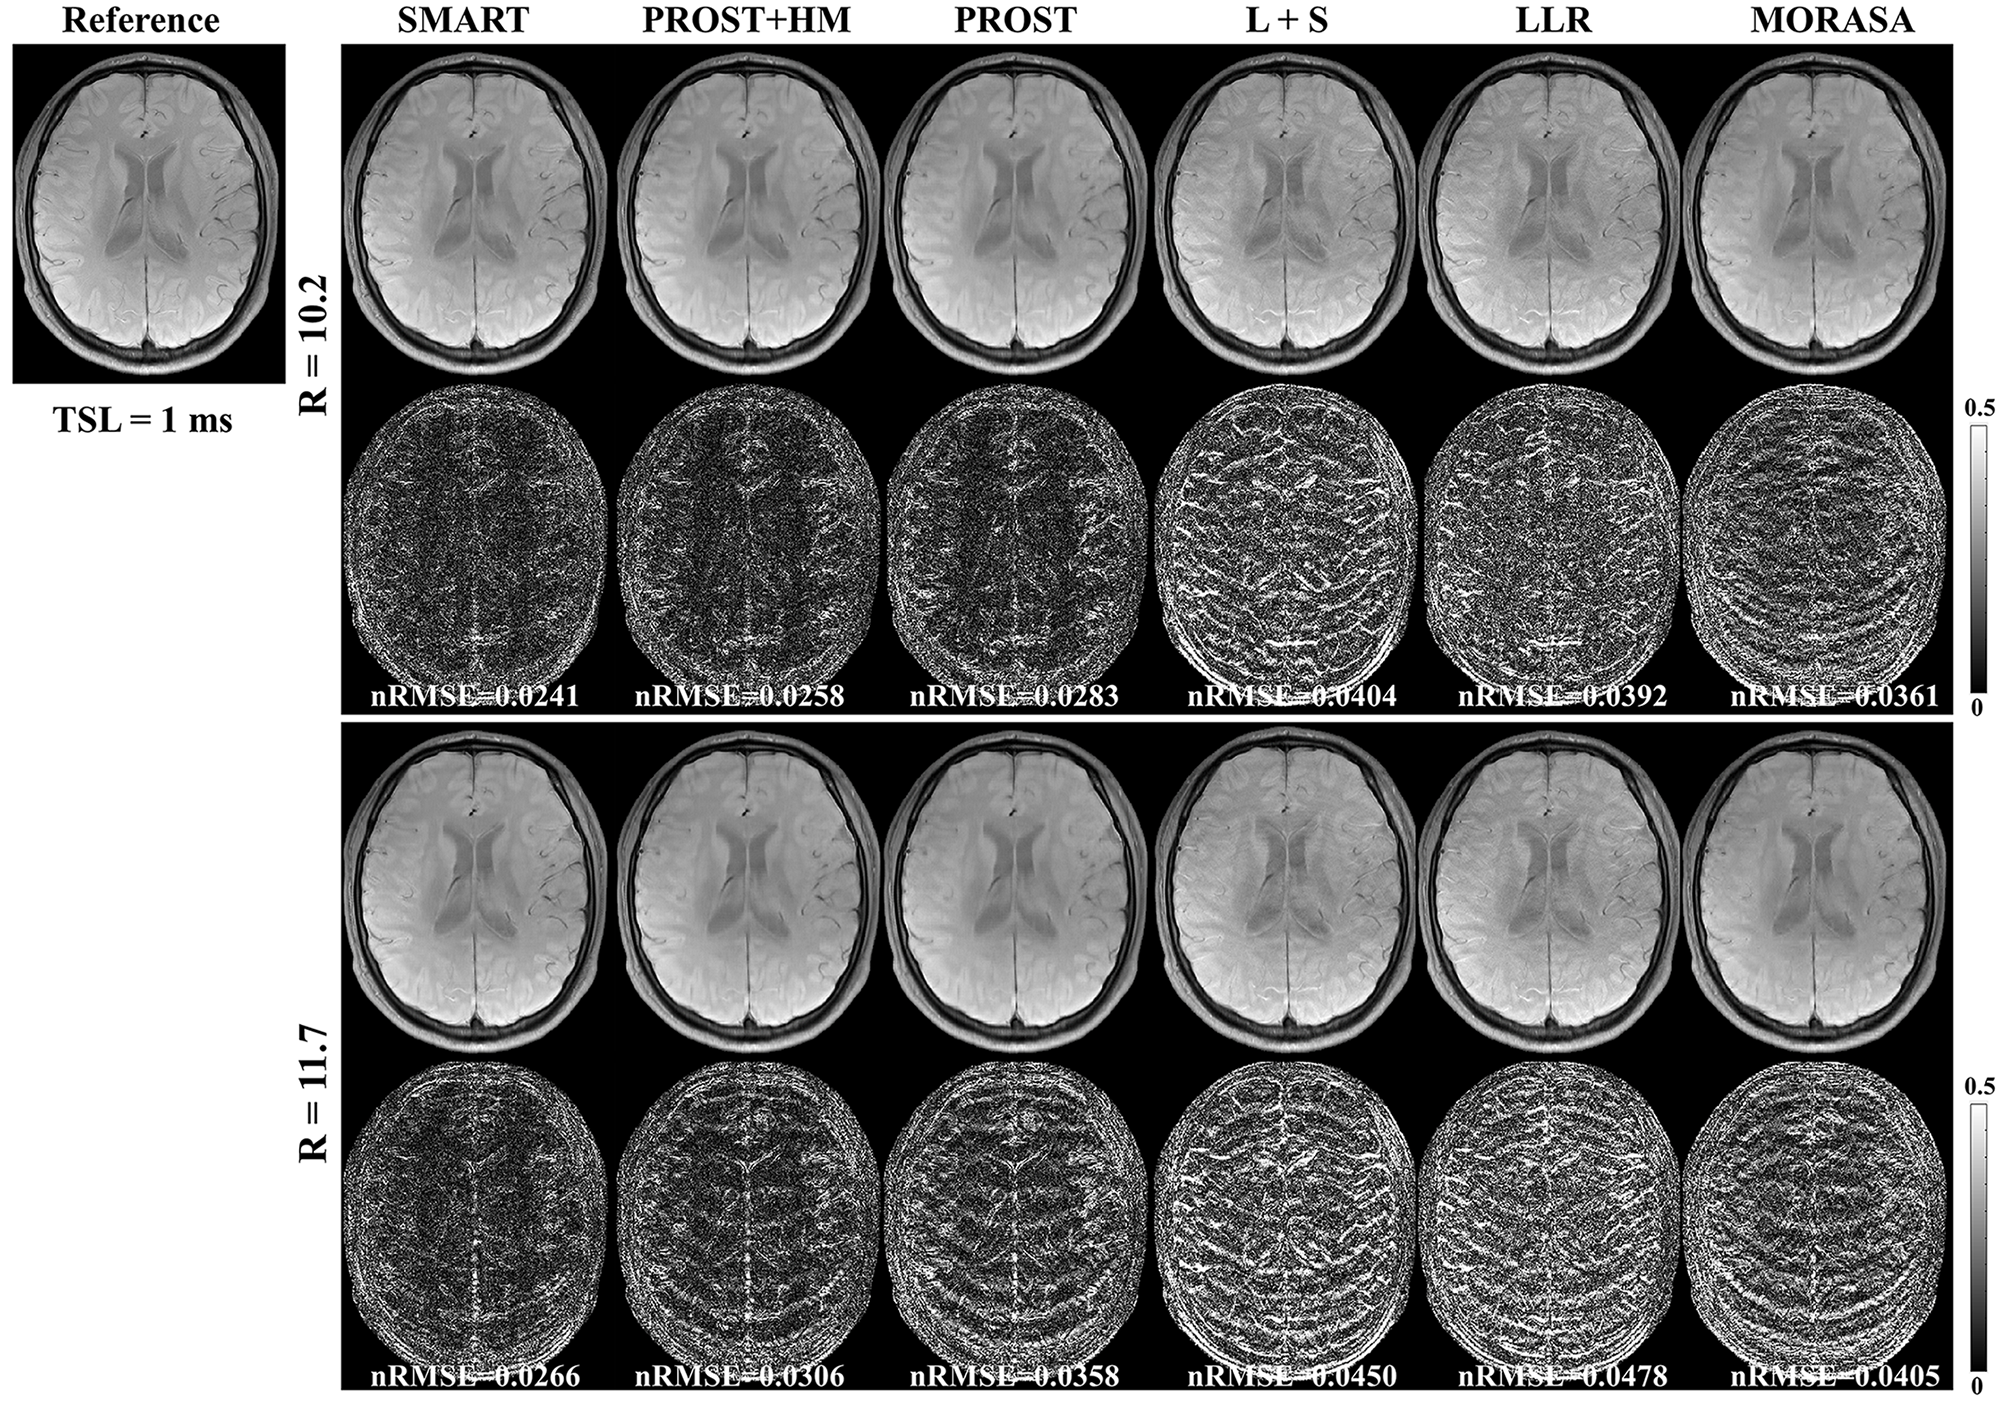

4.2.2 Higher acceleration with 10.2-Fold and 11.7-Fold

The reconstructed -weighted images and the corresponding error images with R = 10.2 and 11.7 are shown in Fig. 5. The nRMSEs are shown at the bottom of each error image. The reconstructed -weighted images using the SMART method have no notable artifacts, even at a high acceleration factor of up to 11.7. The related errors remain noise-like, and the nRMSEs are less than 3. Noticeable aliasing artifacts can be observed from the images or error maps using the PROST+HM, PROST, L+S, LLR, and MORASA methods at different TSLs. The corresponding maps are shown in supplementary information Fig. S3. Table 2 shows the average HFEN, SSIM, and PSNR values for all reconstructed -weighted images. The proposed SMART method qualitatively achieves the best performance among the six methods, especially at R = 11.7.

| Metrics | SMART | PROST+HM | PROST | L+S | LLR | MORASA | |

|---|---|---|---|---|---|---|---|

| 10.2 | HFEN | 0.2558 | 0.2953 | 0.3360 | 0.4057 | 0.4369 | 0.3459 |

| SSIM | 0.9728 | 0.9688 | 0.9637 | 0.9582 | 0.9542 | 0.9674 | |

| PSNR | 40.3712 | 39.4523 | 38.5946 | 36.8233 | 35.3039 | 37.8079 | |

| 11.7 | HFEN | 0.2817 | 0.3460 | 0.4134 | 0.4527 | 0.5148 | 0.3762 |

| SSIM | 0.9701 | 0.9640 | 0.9578 | 0.9533 | 0.9472 | 0.9634 | |

| PSNR | 39.6822 | 38.1819 | 36.8288 | 35.9089 | 33.6896 | 37.2335 |